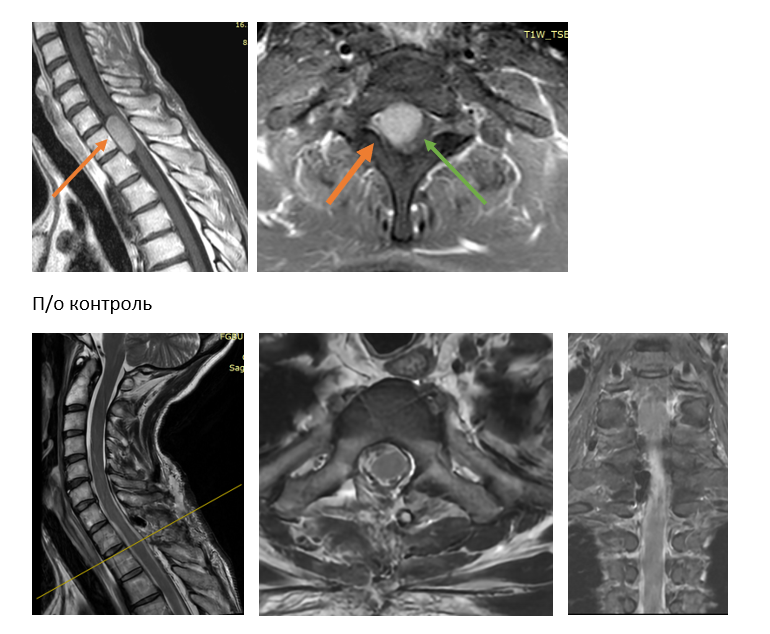

После комплексного обследования и госпитализации в городскую клиническую больницу №1 было выявлено объёмное образование в шейно-грудном отделе спинного мозга (на уровне C7-Th2 позвонков). Пациентка была направлена на хирургическое лечение в Новосибирский научно-исследовательский институт травматологии и ортопедии им. Я.Л. Цивьяна Минздрава России.

«Особенно сложными в хирургическом плане считаются вентрально расположенные менингиомы, т.е. опухоли, расположенные спереди по отношению к спинному мозгу — как в случае нашей пациентки. Поскольку их удаление сопряжено с риском высоких неврологических осложнений, ограничением доступа (хирургической атаки) во время операции и визуализацией опухолей», — объясняет врач-нейрохирург Иван Копылов.

«Достигнуто тотальное (полное) удаление опухоли с последующей морфологической верификацией. Макроскопически опухоль соответствует менингиоме, что при подтверждении диагноза гистологическим исследованием не потребует дальнейших методов лечения — то есть проведения химио- и лучевой терапии. Пациентка переведена в палату в день операции, а после выписки направлена на восстановительное лечение в реабилитационный центр», — говорит Иван Копылов.